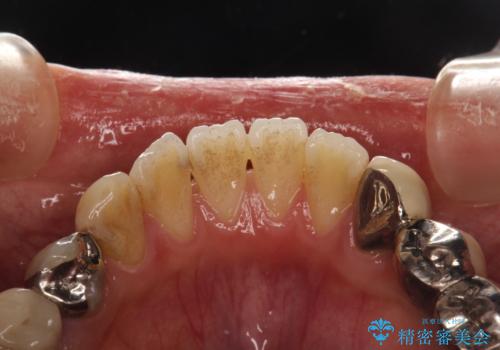

治療のスタート前に着色・ステインをPMTCできれいに除去

- 今まで歯科医院でのクリーニングを受けたことがないとの事でした。これから、虫歯治療が開始されるため、まずは全体的にクリーニングを希望されました。PMTC60分コースを行いました。

歯の表面に、茶色く色が残っている所がありますが、これは詰め物の変色の所と、虫歯になっている所です。以前に、CR(コンポジットレジン)による虫歯治療がされています。

CRは経年的劣化や、着色してしまうことがあります。PMTCでクリーニングを行うと、古いCRが目立つことがあるため、気になる際は詰め替えを行います。

茶色くなっている部分が、着色なのか、劣化なのか、虫歯によるものなのかは判別が難しいことがあります。そのため、定期的にPMTCを行うことで状態の確認が的確に行えます。